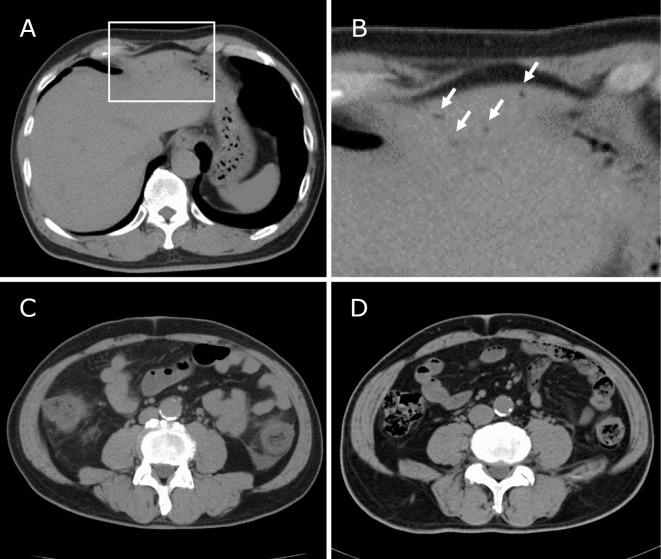

We herein report a case of Brachyspira pilosicoli-caused severe colitis presenting with portal venous gas. A 75-year-old man was admitted because of a fever, severe abdominal pain and bloody diarrhea. He was negative for anti-HIV antibodies. He had been in close contact with a dog earlier. Abdominal computed tomography detected severe wall-thickening and fat-stranding of the entire colon accompanied by portal venous gas. A smear examination of his stool showed many Gram-negative spiral rods, suggesting intestinal spirochetosis. A polymerase chain reaction assay using stool samples detected an amplified band specific for B. pilosicoli. He responded well to antimicrobial agents including metronidazole.

我们在此报告一例由柔毛短螺旋体引起的伴有门静脉积气的严重结肠炎病例。一名75岁男性因发热、严重腹痛和血性腹泻入院。他的抗HIV抗体检测为阴性。他此前曾与一只狗密切接触。腹部计算机断层扫描显示整个结肠严重壁增厚和脂肪浸润,并伴有门静脉积气。他的粪便涂片检查显示有许多革兰氏阴性螺旋杆菌,提示肠道螺旋体病。使用粪便样本进行的聚合酶链反应检测到一条对柔毛短螺旋体特异的扩增条带。他对抗菌药物包括甲硝唑反应良好。